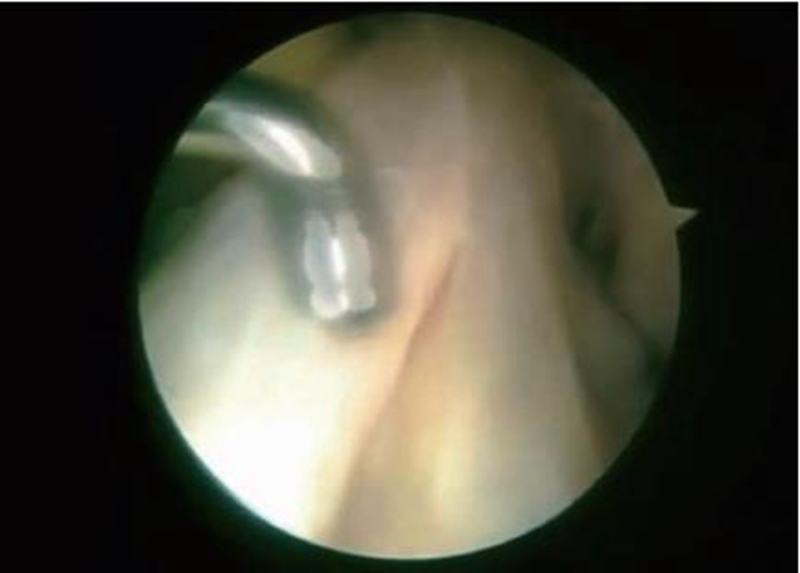

目前为止,双束重建MRI影像学研究还比较匮乏,但ACL的MRI影像显示其有双束或多束结构的并不在少数(图3)。如果韧带断裂,又希望恢复到最佳状态,更优选择应该是能很好地重建其天然结构的解剖双束重建技术(图4)。

图4 ACL双束重建的关节镜下所见